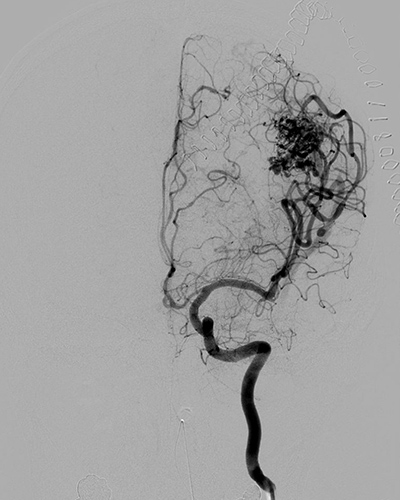

- 脳動静脈奇形

-

脳動静脈奇形(AVM)の脳外科治療には主に3つの方法があります。1)開頭手術による外科的摘出、2)血管内治療(カテーテルを用いた塞栓術)、3)定位放射線治療(ガンマナイフなど)です。AVMの大きさや部位、患者の状態によってこれらの治療を単独もしくは組み合わせて行います。

左前頭葉AVM

術前

術後